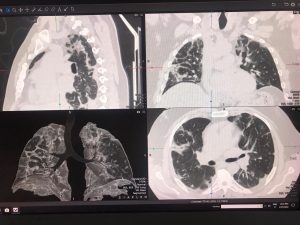

Per conoscere il quadro polmonare nel periodo successivo alla fase di polmonite virale, il Servizio di Diagnostica per Immagini del Fatebenefratelli di Benevento, diretto dal dott. Carmine Manganiello, ha applicato un protocollo di studio del torace con la TAC di ultima generazione in grado di predire l’evoluzione verso la fibrosi polmonare e prevenirne le conseguenze.

Questo percorso consente di apprezzare le alterazioni della struttura polmonare simili alla fibrosi e di confrontare il volume polmonare ben areato con il volume polmonare interessato dalle lesioni della pregressa polmonite interstiziale.

Attraverso la valutazione TAC di tipo quantitativo del torace dei pazienti guariti dalla polmonite interstiziale da COVID-19 è possibile dare indicazioni allo pneumologo e al fisiatra circa la terapia più appropriata per prevenire la fibrosi polmonare.